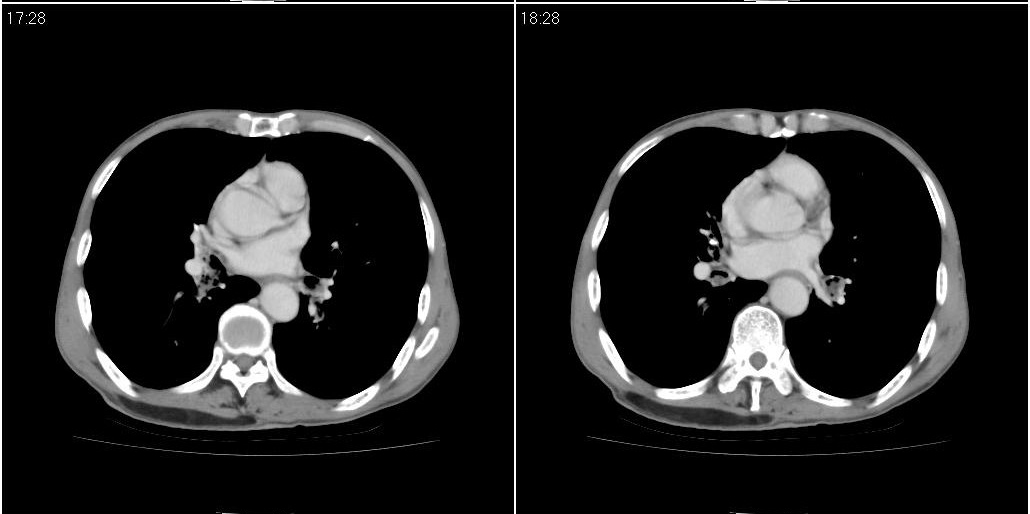

标题: CT25416:男性,70岁。胸片发现右下肺斑片状阴影

以下是ct检查的情况:

考虑右肺下叶炎症可能性大?未除占位,建议增强。右下肺肺不张

右下胸壁皮下气肿。